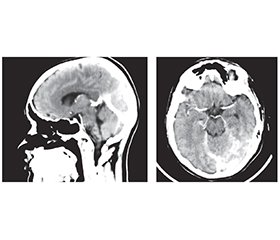

Церебральний венозний тромбоз: сучасний менеджмент і презентація клінічного випадку

Церебральний венозний тромбоз є достатньо рідкісним типом порушення мозкового кровообігу і являє собою наявність тромбу у венозних синусах твердої оболонки й венах головного мозку. Церебральний венозний тромбоз найчастіше зустрічається у пацієнтів молодого віку, здебільшого у жінок. Фактори ризику церебральних венозних тромбозів можуть бути транзиторними або хронічними. До ключових належать статево-специфічні гормональні зміни: пероральна контрацепція і гормональна (переважно естрогенна) терапія, вагітність, інфекції, дегідратація, онкологічні, гематологічні й автоімунні захворювання. Найпоширеніший симптом тромбозу венозних синусів — інтенсивний головний біль, що є відображенням розвитку внутрішньочерепної гіпертензії; іншими симптомами можуть бути: фокальний неврологічний дефіцит, епілептичні напади, втрата або зміна свідомості до коми, порушення зору, менінгеальний синдром. Магнітно-резонансна томографія і магнітно-резонансна венографія є найбільш точними й високочутливими методами діагностики тромбозу церебральних венозних синусів, однак для підвищення вірогідності діагностики слід зважати і на результати інших методів дослідження, включно з комп’ютерною томографією і КТ-ангіографією. Тромби присутні у вигляді дефектів наповнення. Частота рецидивів тромбозів венозних синусів коливається від 1 до 4 % на рік, але вищий ризик може бути в осіб із тяжкою тромбофілією, включно зі злоякісними новоутвореннями. Лікування гострої стадії починається з парентерального введення низькомолекулярних гепаринів із подальшим переходом до пероральних антикоагулянтів протягом 3–12 місяців для посилення реканалізації та запобігання рецидиву. Жінкам із тромбозом церебральних венозних синусів у зв’язку із застосуванням комбінованих гормональних контрацептивів або вагітністю слід утримуватися від продовження або поновлення гормональної контрацепції через підвищений ризик рецидиву. Ми також наводимо клінічний випадок протяжного тромбозу верхнього сагітального синуса з поширенням тромбу в лівий поперечний, сигмоподібний синуси та внутрішню яремну вену у молодої жінки на тлі прийому гормональних естрогенвмісних препаратів зі сприятливим результатом.

Cerebral venous thrombosis is a fairly rare type of cerebral circulatory disorder; there is a thrombus in the venous sinuses of the dura mater and veins of the brain. Cerebral venous thrombosis is most common in young patients, more often in women. Risk factors for cerebral venous thrombosis can be transient or chronic. The key ones include sex-specific hormonal changes: oral contraception and hormonal (mainly estrogen) therapy, pregnancy, infections, dehydration, cancer, hematologic and autoimmune diseases. The most common symptom of venous sinus thrombosis is intense headache, which is a reflection of the development of intracranial hypertension; other symptoms may be focal neurological deficit, epileptic seizures, loss or change of consciousness up to coma, visual impairment, meningeal syndrome. Magnetic resonance imaging and magnetic resonance venography are the most accurate and highly sensitive methods for diagnosing cerebral venous sinus thrombosis, but to increase the reliability of the diagnosis, the results of using other research methods should be taken into account such as computed tomography and computed tomography angiography. Thrombi are present in the form of filling defects. The recurrence rate of venous sinus thrombosis ranges from 1 to 4 % per year, but the risk may be higher in individuals with severe thrombophilia, as well as malignant neoplasms. Treatment of the acute phase begins with parenteral administration of low-molecular-weight heparins followed by a transition to oral anticoagulants for 3–12 months to enhance recanalization and prevent recurrence. Women with cerebral venous sinus thrombosis resulting from the use of combined hormonal contraceptives or pregnancy should refrain from continuing or resuming hormonal contraception due to an increased risk of recurrence. We also present a clinical case of extensive superior sagittal sinus thrombosis with the spread of the thrombus to the left transverse, sigmoid sinuses and internal jugular vein in a young woman on the background of taking hormonal estrogen-containing drugs, with a favorable outcome.